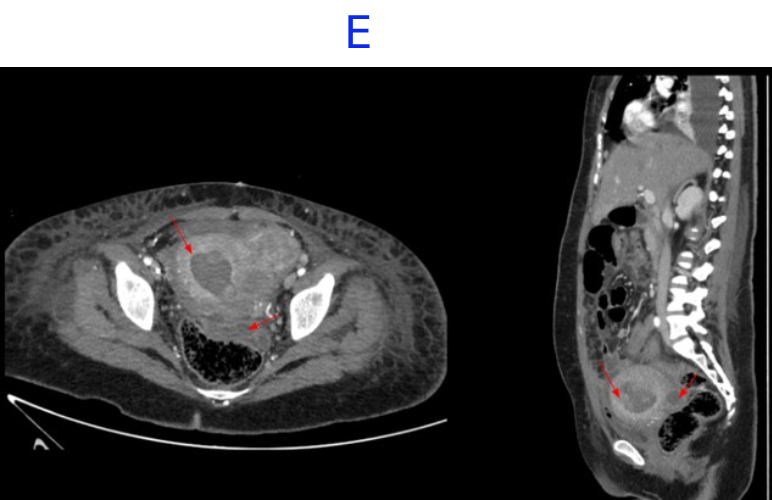

• E. Bulky uterus with a hypodense submucosal lesion protruding into the endometrial cavity from the fundus showing heterogeneous enhancement - infected vs infarcted fibroid. Abnormally enhancing endometrial lining with hypodense content within the endometrial cavity - possible endometritis with pyometra. Left sided pyosalpinx.

• Bulky uterus with a hypodense submucosal lesion protruding into the endometrial cavity from the fundus showing heterogeneous enhancement - infected vs infarcted fibroid.

• Abnormally enhancing endometrial lining with hypodense content within the endometrial cavity - possible endometritis with pyometra

• Left sided hydro/pyosalpinx.